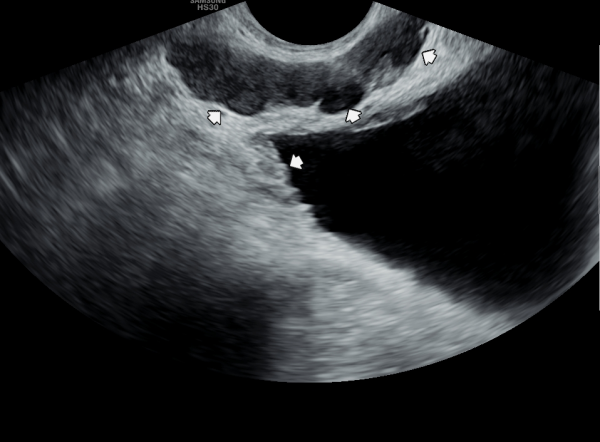

5년후 내원 당일 정낭의 경직장 전립선 초음파 검사상 정낭의 낭종들이 커지고 있는 사진입니다.

A transrectal prostate ultrasound image of the seminal vesicles taken on the day of the visit five years later, showing enlargement of seminal vesicle cysts.